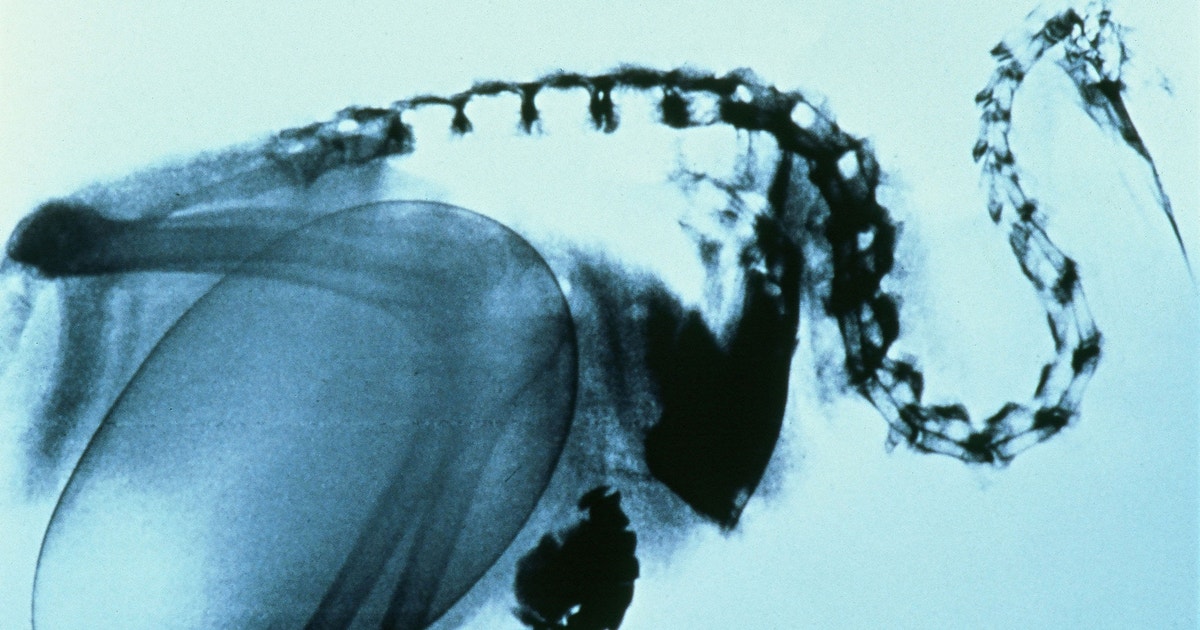

Look at this poor unfortunate little bird

Why Is the Kiwi’s Egg So Big?

This small(ish) bird lays one of the largest eggs in the bird world. New research might hold the keys to solving this long-standing mystery.